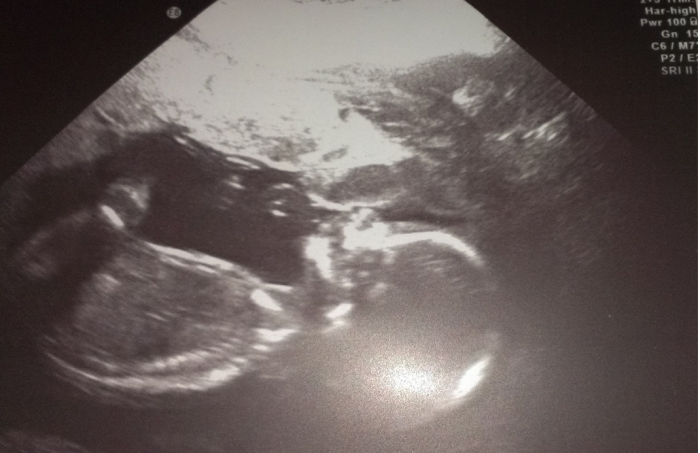

Tak ještě sem dám fotku našeho miminka-jak ukazuje dlouhý nos. To dítě bude mít smysl pro humor

Ahoj holky,tak se hlásím z včerejšího velkýho utz,dneska jsme 21+0 všechno v pořádku,tak teď už si to budeme jen užívat :-) Teď vyřázíme ke švagrové,ta čeká prcka v září,tak budeme mít v rodině veselo :-) Přikládám vám foto :-) Jinak Gilmorovi děvčata taky můžu,ale teď co jsem doma tak čumím v televizi snad na všechno :-)